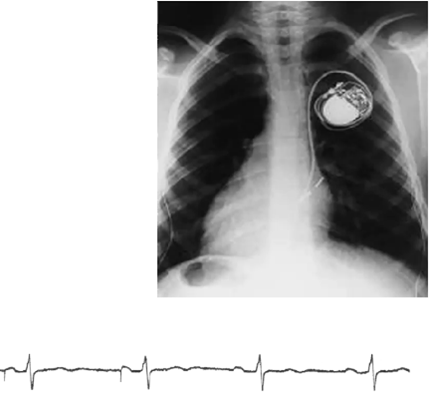

Vad visar bilden?

Pacemaker